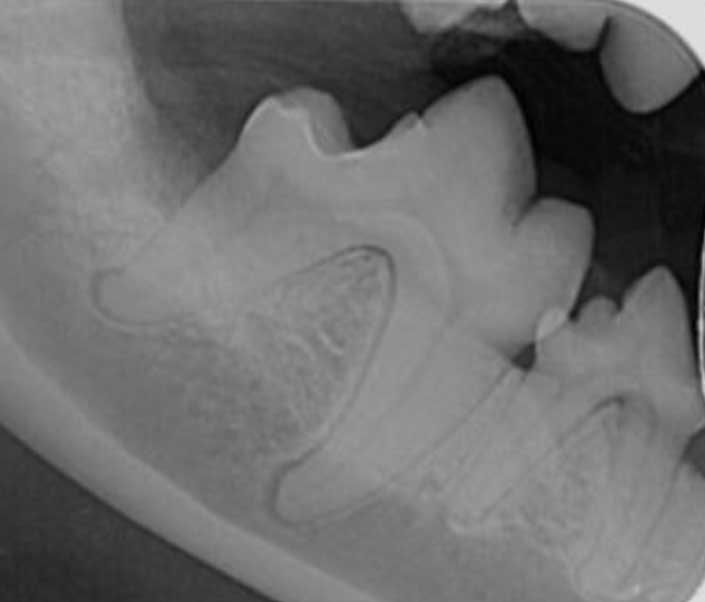

Figure 4. Dental radiographs of left and right mandibular first molar teeth in a five-year-old dog with moderate periodontal disease. The mandibular second molar teeth were extracted and open root planing performed on the distal aspect of the distal roots of the first molar teeth. The owner was very motivated to salvage the teeth and committed to twice-daily brushing.

Figure 5. Repeat radiographs of the same patient as Figure 4, taken five months after periodontal therapy. The vertical bone defects have filled with new bone and periodontal ligament has redeveloped around the root, indicating successful treatment of periodontal disease. It should be noted a degree of horizontal bone loss is still evident, which is to be expected as alveolar bone height is known to be a more permanent change.